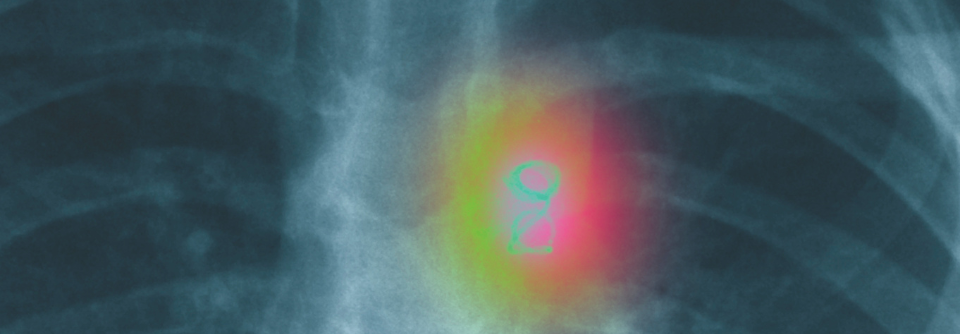

Krebserkrankung

Pfunde schaden früh

Übergewichtige Kinder und Jugendliche haben ein höheres Risiko, ein Rezidiv ihrer Krebserkrankung zu erleiden oder sogar daran zu sterben. Dies galt…

Onkologie und Hämatologie , Pädiatrie